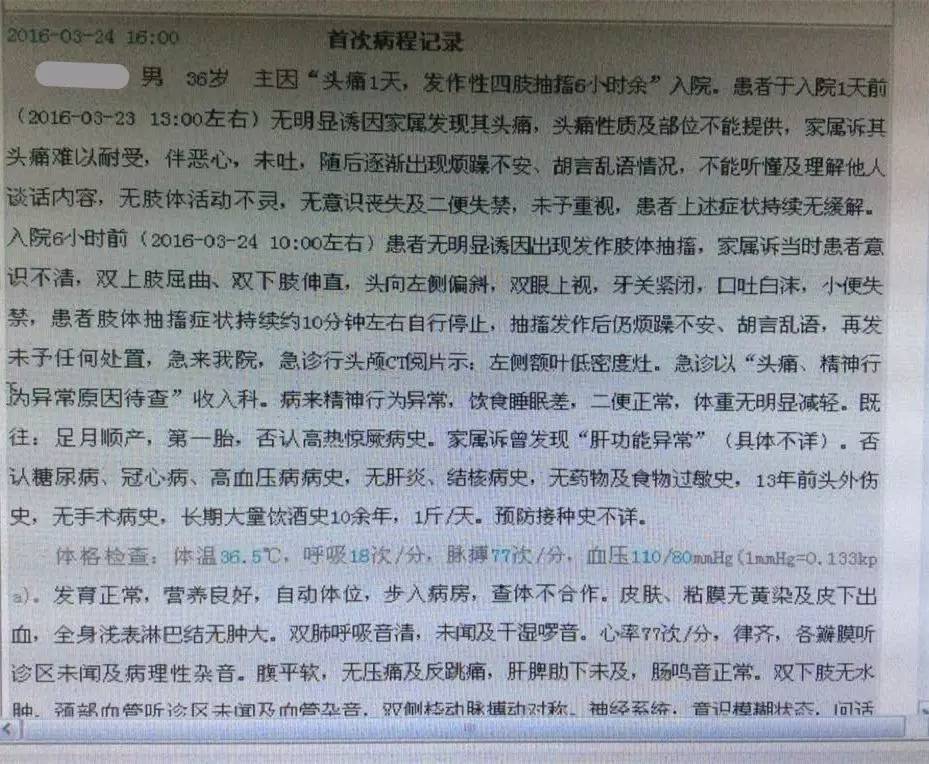

患者:男性,36岁,主因“头痛1天,发作性四肢抽搐6小时余”于2016年3月24号入院。

现病史:患者于入院1天前无明显诱因由家属发现头痛,头痛性质及部位不能提供,家属诉其头痛难以耐受,伴恶心、未呕吐,随后逐渐出现烦躁不安、胡言乱语等情况,不能听懂及理解他人谈话内容,无肢体活动不灵,无意识丧失及二便失禁,未予以重视,患者上述症状持续无缓解。入院6小时前患者无明显诱因出现发作性肢体抽搐,家属诉当时患者意识不清,双上肢屈曲、双下肢伸直,头向左侧偏斜,双眼上视、牙关紧闭、口吐白沫、小便失禁,患者肢体抽搐持续约10分钟自行停止,抽搐发作后仍烦躁不安、胡言乱语,再发后未予以任何处置,急来我院,行头颅CT示左额叶低密度影,急诊以“头痛、精神行为异常原因待查”收入我科。患者自发病以来,精神行为异常,饮食睡眠差,大小便正常。

既往:13年前头颅外伤史。

查体:生命体征平稳,意识模糊,双瞳孔正大等圆,光反射灵敏,余脑神经查体欠合作。四肢肌力、肌张力检查欠合作,双侧腱反射存在对称,感觉运动查体欠合作,双侧病理征(+)。颈抵抗。

辅助检查:

2016-3-24血常规示,白细胞计数10.35×109/L,淋巴细胞百分比1.4%,中性粒细胞百分比93.2%,中性粒细胞绝对值9.65×109/L。

2016-3-25生化全项示,AST47.5U/L,GGT128U/L。血沉80mm/h,CRP453mg/L。

2016-3-26甲功三项(-),术前四项(-),梅毒螺旋体抗体(+)。

2016-3-25腰穿压力>300mmH2O,细胞计数80×106/L,脑脊液蛋白5.432g/L,葡萄糖0.03mmol/L,氯化物112.3mmol/L,脑脊液IgG601mg/L。脑脊液墨汁染色(-),抗酸染色(-),间皮细胞30%,单核细胞30%,多核细胞40%。

▼患者病情描述